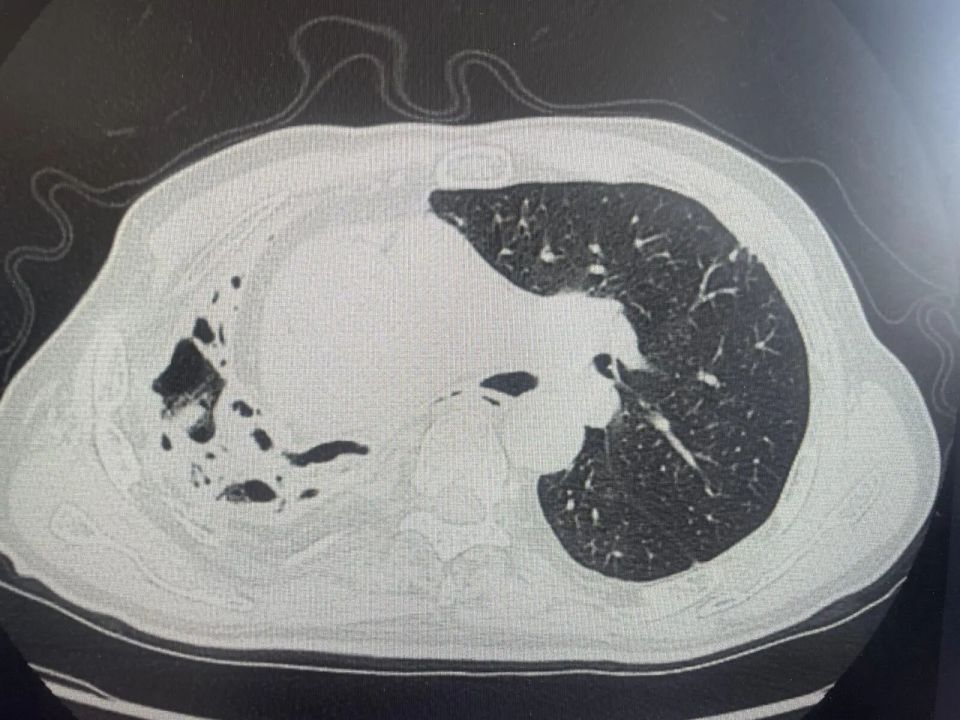

上医院做了CT检查

显示王大伯右肺已严重毁损

呈现出典型的蜂窝状改变

肺功能受损严重

肺部CT提示右肺毁损、蜂窝状改变